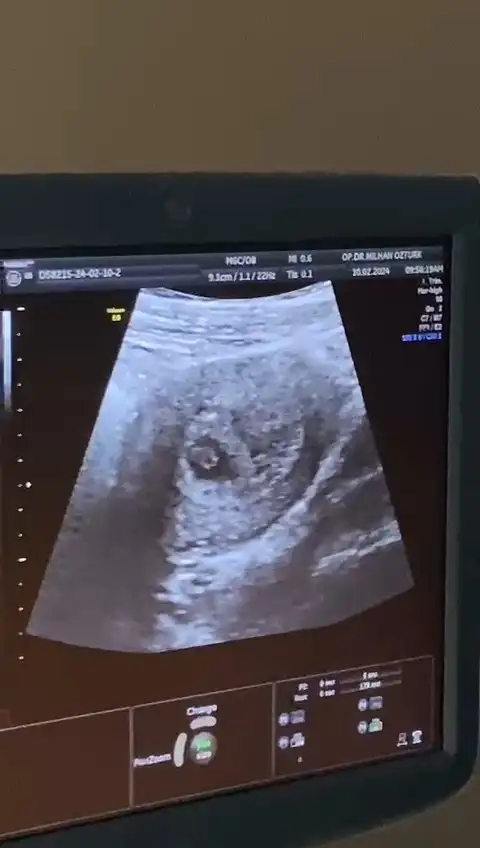

Aha neymiş cinsiyeti kızKızlar ben bugün doktoruma gittim dayanamadım muayene oldum nerdeyse 3 hafta önde imiş bebek ve sürpriz bir şekilde cinsiyeti öğrendim şaka gibi

Kızlar ben bugün doktoruma gittim dayanamadım muayene oldum nerdeyse 3 hafta önde imiş bebek ve sürpriz bir şekilde cinsiyeti öğrendim şaka gibi